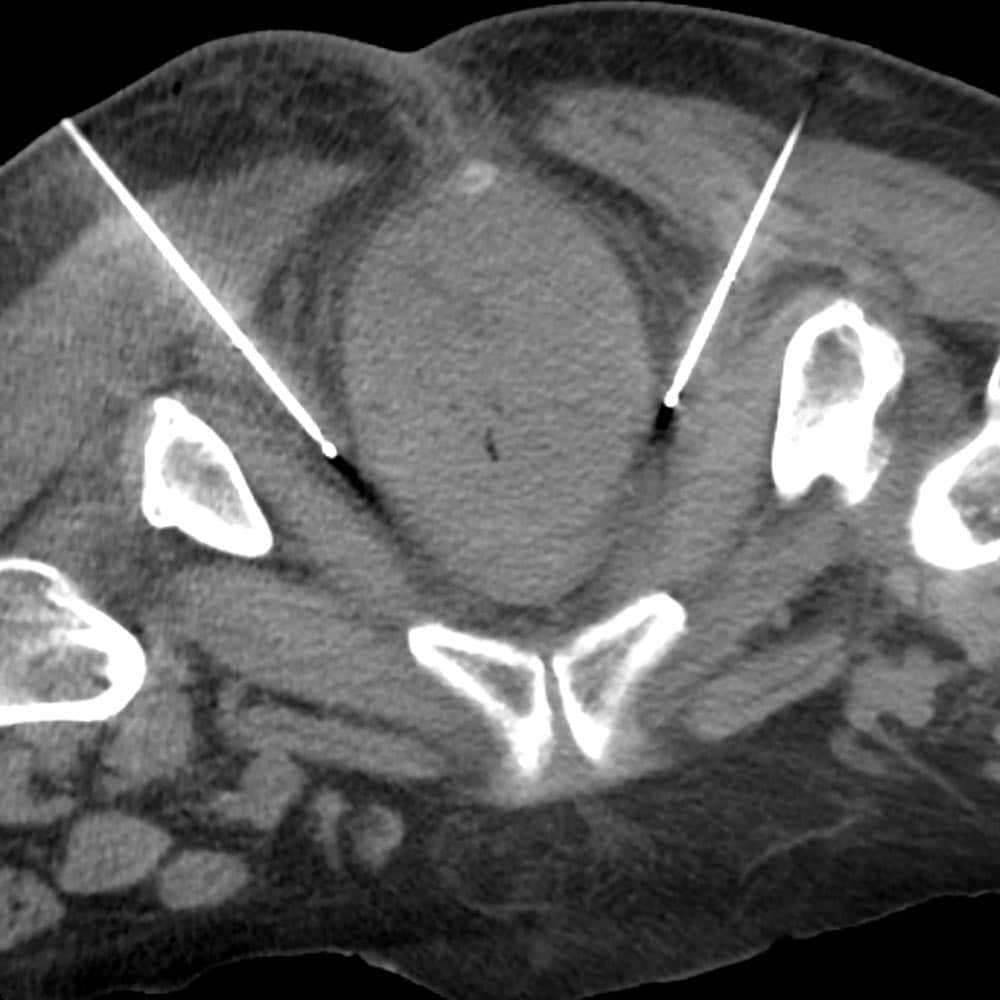

neurolytic blocks probed placed for pudendal nerve cryoablation

Pudendal nerve cryoablation

The pudendal nerve block is a specialized neurolytic procedure designed to relieve chronic pain associated with pudendal neuralgia, a condition that can cause severe pain in the pelvic and genital areas. This block targets the pudendal nerve, which is responsible for sensation in these areas, and can alleviate pain from conditions such as childbirth injury, pelvic surgery, or nerve entrapment.

Performed under imaging guidance, the pudendal nerve block involves the injection of a neurolytic agent near the pudendal nerve to interrupt pain signals effectively. Cryotherapy (cold treatment) may be used in some cases, which involves freezing the nerve to achieve pain relief. Patients undergoing a pudendal nerve block often experience improved quality of life and relief from chronic, debilitating pelvic pain.